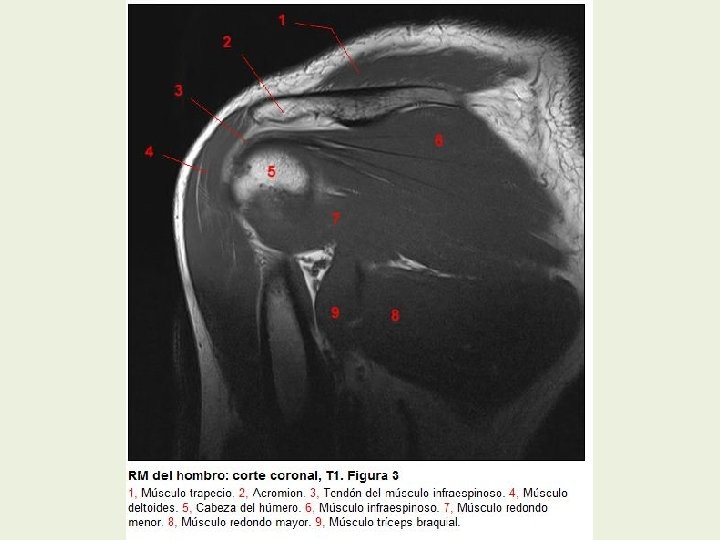

Hombro Cortes coronales RMN